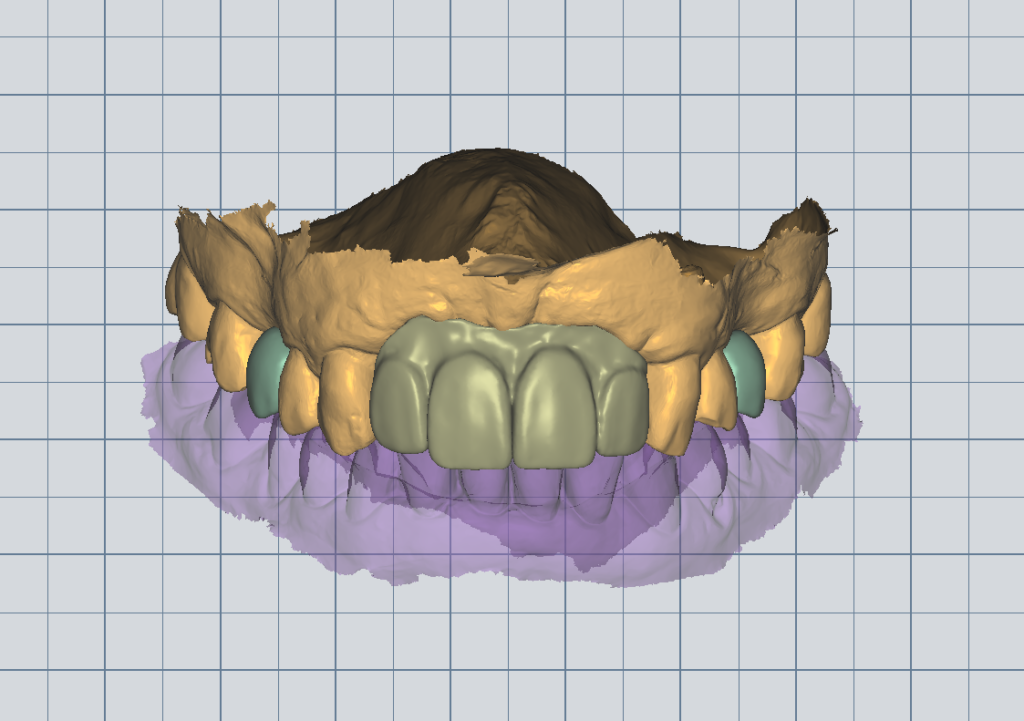

A patient once came to our clinic with four missing upper front teeth (both central and lateral incisors). The situation caused major aesthetic distress and significantly affected her confidence.

To restore her smile, we placed two implants in the lateral incisor areas and fabricated an implant-supported bridge from lateral to lateral.

The transformation was remarkable. The patient regained the ability to smile, speak, and live confidently again. Cases like this show how restoring teeth can truly change a person’s life.